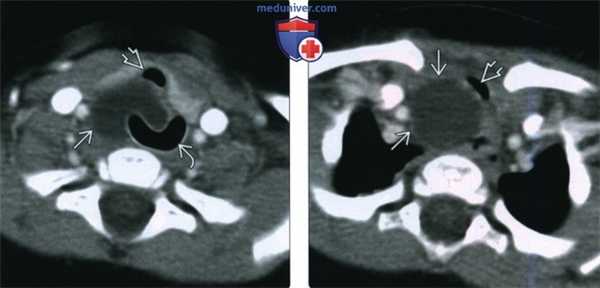

(Слева) При аксиальной ACT с АСУ у 6-месячного ребенка с рецидивирующим стридором в правой половине шеи визуализируется кистозное образование, расположенное глубже правой доли щитовидной железы и трахеи. Киста податлива и располагается вдоль заднего края ларингеальной маски. Было выполнено оперативное вмешательство, подтвердилась атипичная правосторонняя киста тимуса.

(Справа) При аксиальной КТ с КУ у этого же пациента определяется киста тимуса, распространяющаяся в верхнее средостение и смещающая трахею влево.